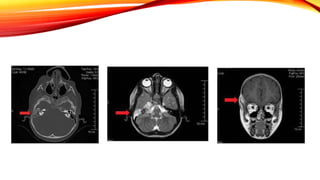

PETROSITIS

• Tromboeflebitis, diseminación

hematógena o extensión directa.

• Otorrea

• Antibioticos y drenaje del vértice

petroso

• Rara

• Puede ocurrir en Apex petroso no

neumatizado, esclerótico, diploico

• Diagnostico y cuadro clínico similar

a Mastoiditis

• Paralisis del Abducens es

extremadamente rara

Triada de

Gradeningo

Dolor

Retroorbitario

Paralisis

Abducens

Otitis media

crónica

ipsilateral